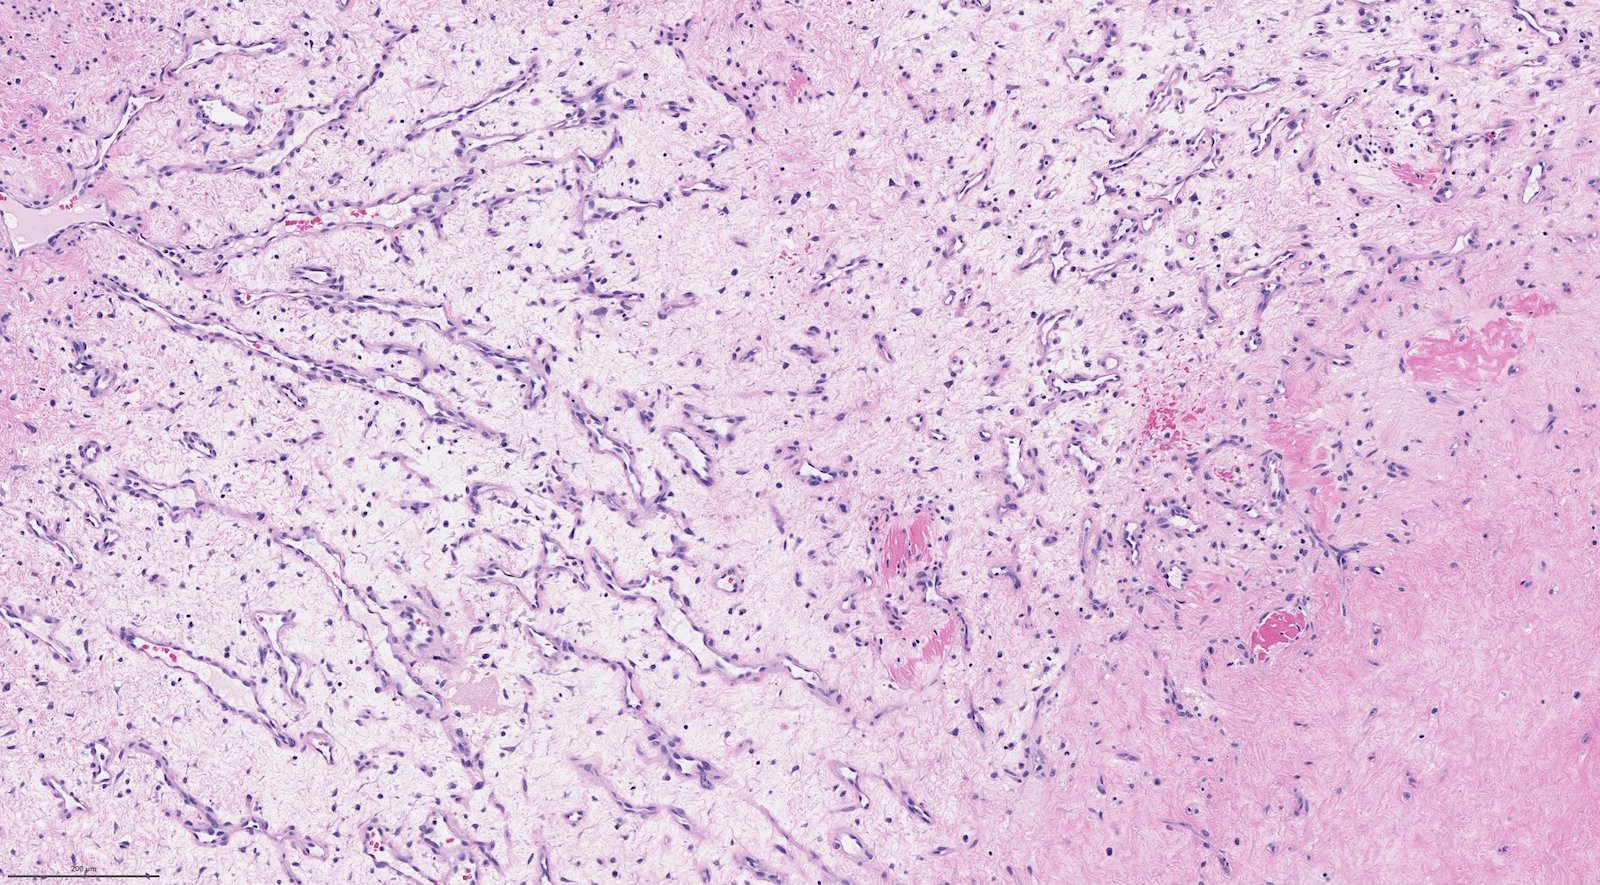

Microscopic (histologic) description

- Benign fibrovascular lesion composed of 2 components

- Vascular space of various sizes, ranging from dilated branching vessel of various thickness to slit-like capillaries

- Fibrous or collagenous stroma with fibroblasts

- Central area of the tumor is typically cellular, composed of fibroblasts or myofibroblasts with spindle, round or stellate morphology

- Stroma can be fibrous, edematous or collagenized

- Fibrinous thrombi may be seen in dilated vessels

- Frequently contain (abundant) mast cells

- Mitotic figures are usually absent

- Reference: Chan: WHO Classification of Head and Neck Tumours, 4th Edition, 2017

Microscopic (histologic) images

Contributed by Bin Xu, M.D., Ph.D.

Contributed by Kelly Magliocca, D.D.S., M.P.H.